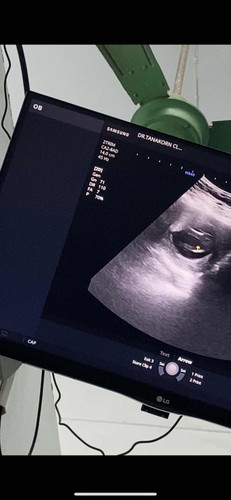

อายุครรภ์13w3d มีลุ้นเป็นลูกสาวไหมค่ะ

คนแรกของแม่ได้ลูกชาย คนที่2พอจะได้ลุ้นลูกสาวไหมค่ะ ใครพอมีประสบการณ์ซาวด์ 13wแบบแม่บ้าง มาแชร์ให้ฟังหน่อยนะคะ

อายุครรภ์เท่ากันเลยค่ะ บ้านนี้ก็อยากได้ลูกสาว คนแรกลูกชายเหมือนกันค่ะ

หมอบอกยังเห็นไม่ชัดค่ะ ยังเล็กมาก ภาพที่โพสลงคือหว่างขาน้องค่ะ แม่อยากให้แม่ๆช่วยพิจารณาดูค่ะ